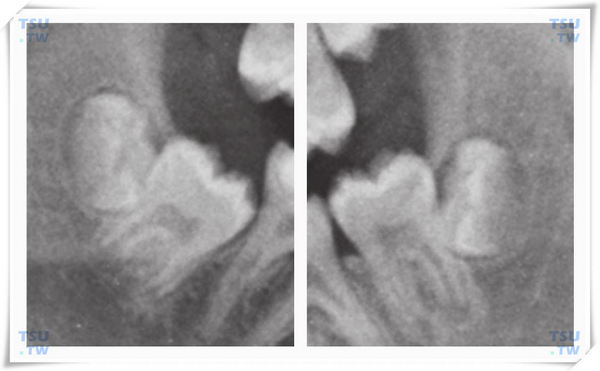

智齿的牙胚在4~5岁时开始形成,7~10岁时开始形成硬组织,此时在X线片上可看到钙化的牙尖,有牙囊存在,此后,牙体硬组织和软组织不断形成,在12~16岁时牙冠发育完成,进入牙根发育期,牙齿